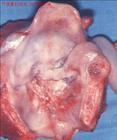

喉癌專題

喉癌的檢查與診斷

喉癌在我國北方比南方發(fā)病率高,城市比農(nóng)村發(fā)病率高,男性多于女性。發(fā)病年齡多在40—70歲之間。

病因病理

· 喉癌的病因病理有哪些

· 誘發(fā)喉癌的因素有哪些?